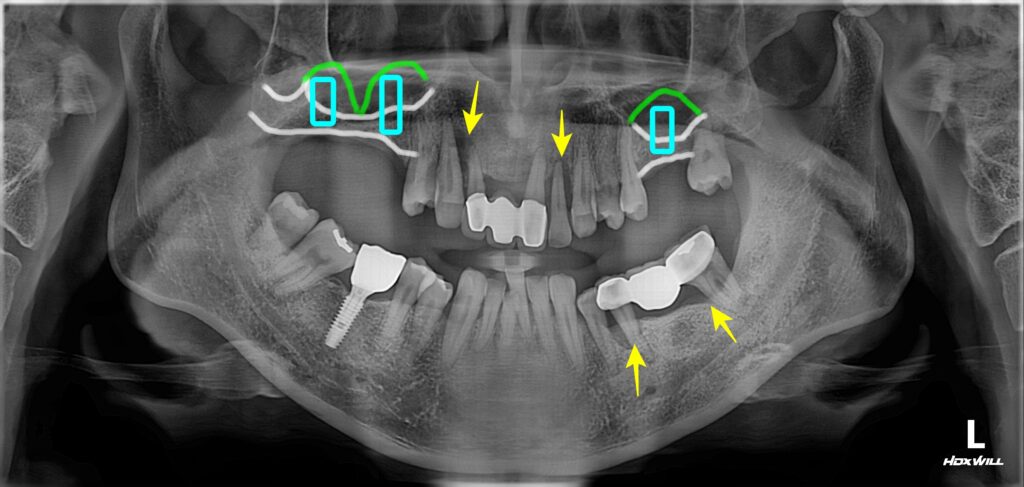

문제점 파악

1. 어금니와 앞니 쪽 잇몸 염증이 심해서 치아가 많이 흔들리고 있었습니다. (노란색 화살 표시)

​해당치아들은 발치를 해야 할 만큼 상태가 많이 안 좋았네요.

​어금니가 먼저 무너지고 어금니가 지지를 해주지 못하니까 앞니 쪽에 많은 힘이 가해져서 결국 앞니가 버티지 못하고 흔들리게 된 것으로 추측이 됩니다.

​​어금니가 건재해야 앞니도 건강합니다.

​상악 어금니의 경우 임플란트 심기에 뼈가 부족해서(흰색 실선) 상악동 거상술을 통해 뼈를 만들어줘야 했습니다. (초록색 실선)

​​상악동 거상술을 통한 뼈이식과 관련된 글 아래에서 확인 바랍니다.^^